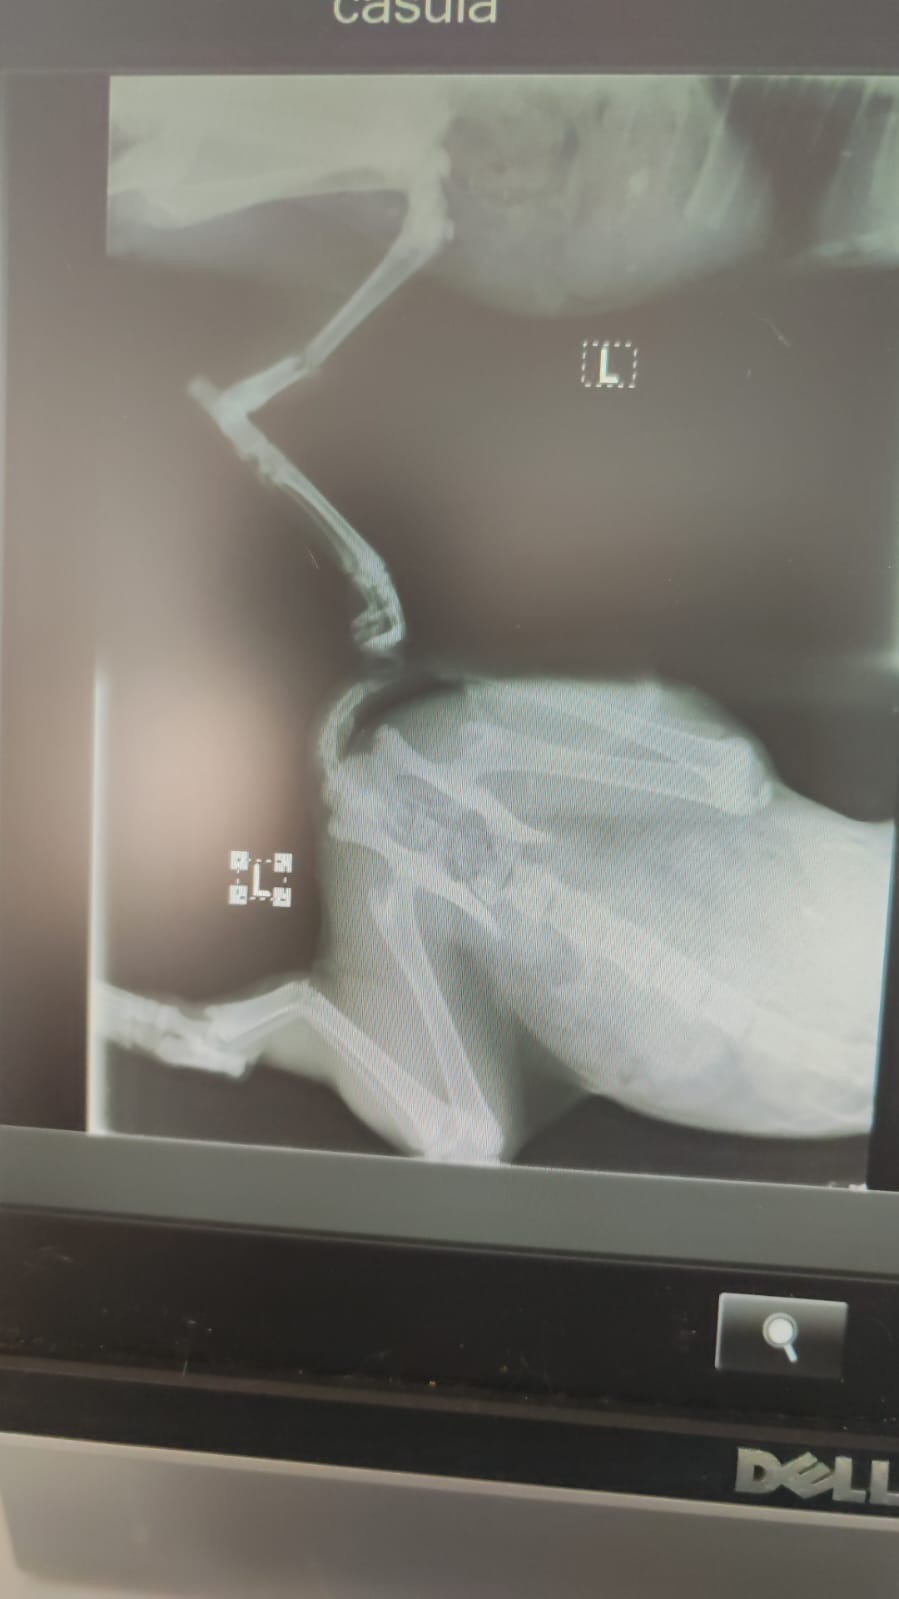

Timmi è un gattino nero di colonia che purtroppo è stato investito e ha la zampina spezzata.

Per salvarla serve un’operazione urgente dal costo di 500 €.